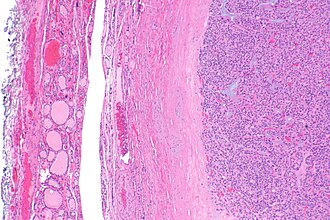

Follicular adenoma. H&E stain. | |

| LM | cellular appearance (low magnification), microfollicles, thick fibrous capsule without invasion, negative for nuclear features of papillary thyroid carcinoma |

- Cellular.

- Thick capsule - key feature.

Negatives.

- No invasion of the capsule - see follicular thyroid carcinoma.

- No nuclear features suggestive of papillary thyroid carcinoma.

The section shows a well-circumscribed lesion encapsulated by a thick fibrous capsule (~0.4 mm thick).

The lesions consists of microfollicles with a dense appearing colloid. The nuclei have round regular nuclear membranes. Small indistinct nucleoli are seen at high power.

Focally, the lesional cells overlap. However, the chromatin is not cleared. Nuclear grooves are not readily apparent and nuclear pseudoinclusions are not readily identified.